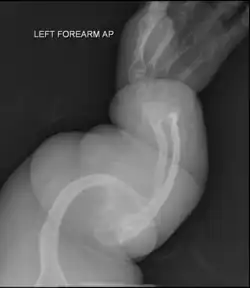

Les aspects radiographiques de l'os contribuent au diagnostic.

Diagnostic radiologique

On observe une transparence excessive des os ainsi que des déformations sur les clichés radiologiques[7]. Ces déformations sont principalement constatées au niveau de :

- la partie diaphysaire de l’os : une corticale diaphysaire mince, une crosse au niveau des os longs ainsi que la présence de plusieurs cals osseux ;

- la hanche avec une protrusion acétabulaire c'est-à-dire une malformation associant une hanche trop profonde et des amplitudes articulaires diminuées ;

- des pieds avec des pieds plats et en valgus c'est-à-dire les membres qui s’écartent vers l’extérieur par rapport à l’axe du corps ;

- des membres supérieurs avec une déformation supérieur à 30° ;

- du crâne avec des os wormiens c'est-à-dire des petits os situés à l'intérieur de divers os constituant le crâne (occiput, pariétal, temporal…) présents en nombre plus important que la normale ;

- du rachis et du thorax avec un thorax plus bombé que la normal et des modifications au niveau des vertèbres telles que des tassements de certaines vertèbres, des vertèbres biconcaves, des scolioses… Lors de fractures, le siège se situe principalement au niveau des membres inférieurs et des vertèbres.